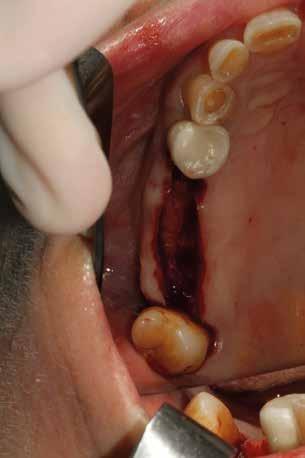

Esempio chirurgico di accesso tra 2 elementi dentari con conformazione della cresta alveolare ampia. Incisione del lembo in cre sta senza scarichi laterali con sollevamento di 2 lembi, palatale e vestibolare; si può notare come quest’ultimo non si estenda oltre

Estrazione di 3 elementi dentari complicata da frattura coronale di 2.4 e presenza di 2 corone protesiche unite su denti pluriradicolati. L’approccio deve prevedere la rimozione delle corone protesiche e la separazione delle radici, semplificando le manovre di estrazione e consentendo di risparmiare i tessuti molli pericoronali e prevenire la frattura

Il rispetto dei tessuti molli consente di ridurre i tempi di guarigione, sebbene a siti più ampi corrisponda un tempo di ripristino o maggiore. Il mantenimento delle corticali vestibolari, palatine e l’assenza di alveolite post-estrattiva riducono l’atrofia ossea.

Un ridotto scollamento dei tessuti molli riduce edema e dolore post operatorio, mentre la preparazione del sito implantare a bassi giri con irrigazione limita il trauma del tessuto osseo.

Una incisione lineare netta si estende coinvolgendo minimamente il dente mesiale e maggiormente in direzione distale, consente di evitare l’esecuzione di incisioni di scarico che provocano una interruzione della vascolarizzazione maggiore, senza ridurre la visibilità del campo operatorio.